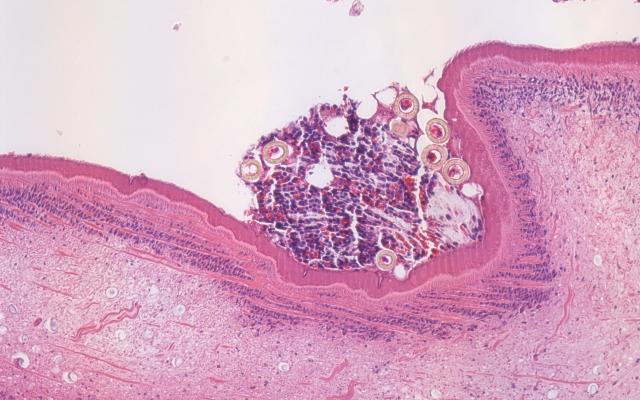

Dit artikel is alleen beschikbaar als PDF.Lees de PDF Artikelinformatie Online verschenen op 3 juni 1950 Citeer dit artikel als Ned Tijdschr Geneeskd. 1950;94:2625 Heb je nog vragen na het lezen van dit artikel? Check onze AI-tool en verbaas je over de antwoorden. ASK NTVG Ook interessant Diagnose in beeld Een 48-jarige vrouw met een appendicitis Beeldquiz Een 48-jarige vrouw met een appendicitis Media Klinik der Gegenwart, 48e aanvulling Meer gerelateerd … Reacties Login om een reactie te plaatsen